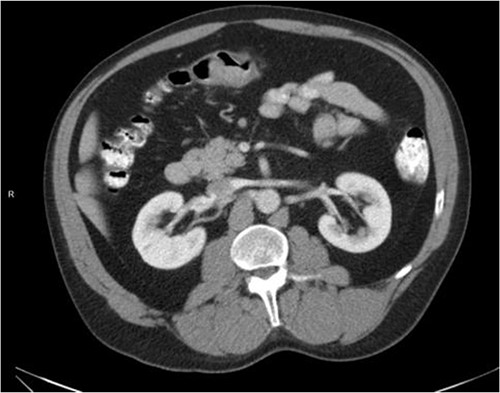

He was then referred to gastroenterology and underwent diagnostic colonoscopy that showed a large polypoid mass in the transverse colon that was partially obstructing. Gastroenterology then obtained a CT scan of the chest, abdomen and pelvis that showed wall thickening of the colon (Figs 1–3). Ultimately when pathology confirmed malignant melanoma, a PET scan was ordered that showed increased uptake at the previously seen and biopsied transverse colon mass (Fig. 4).

Axial CT scan with IV contrast showing thickened transverse colon.